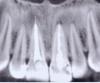

Добрый день. У меня первый зуб справа сверху стал темным после удаления нерва и пломбирования канала(~ 3 года назад). Недавно решила обратиться в частную клинику для его отбеливания. Сделала КТ (один из снимков оттуда собственно и выложен), сделали рентген, врач сказала, что воспаление у корней обеих единиц + штифты выведены за корень, что тоже плохо. Итак спереди 2 зуба: один черный, не болит, второй белый(делали ~1 год назад), тоже мертвый, но болит при нажатии, болит десна сверху него. Врач сказала действия такие: вытаскиваем штифты из обоих зубов, прочищаем хорошенько каналы, пломбирует их заново, ждем, что будет с воспалением (лучше бы распухла десна, чтобы сделать разрез и убрать оттуда гной, но пока десна не распухает). Говорит, что от темного зуба может мало что остаться и придется ставить коронку (не хочется конечно, но как врач скажет). Была еще у другого врача (которая делала белый зуб), она сказала воспаление или снять электрофорезом, или резать десну. Делали оба зуба разные врачи в разное время. Подскажите, что бы делали вы или какие-нибудь просто рекомендации. И еще такой вопрос: может ли воспаление быть вызвано штифтами? Я вот не могу вспомнить, было ли оно до того, как начали лечить эти зубы. Заранее спасибо за любые ответы.

(на снимке вроде зубы зеркально, не знаю даже точно)